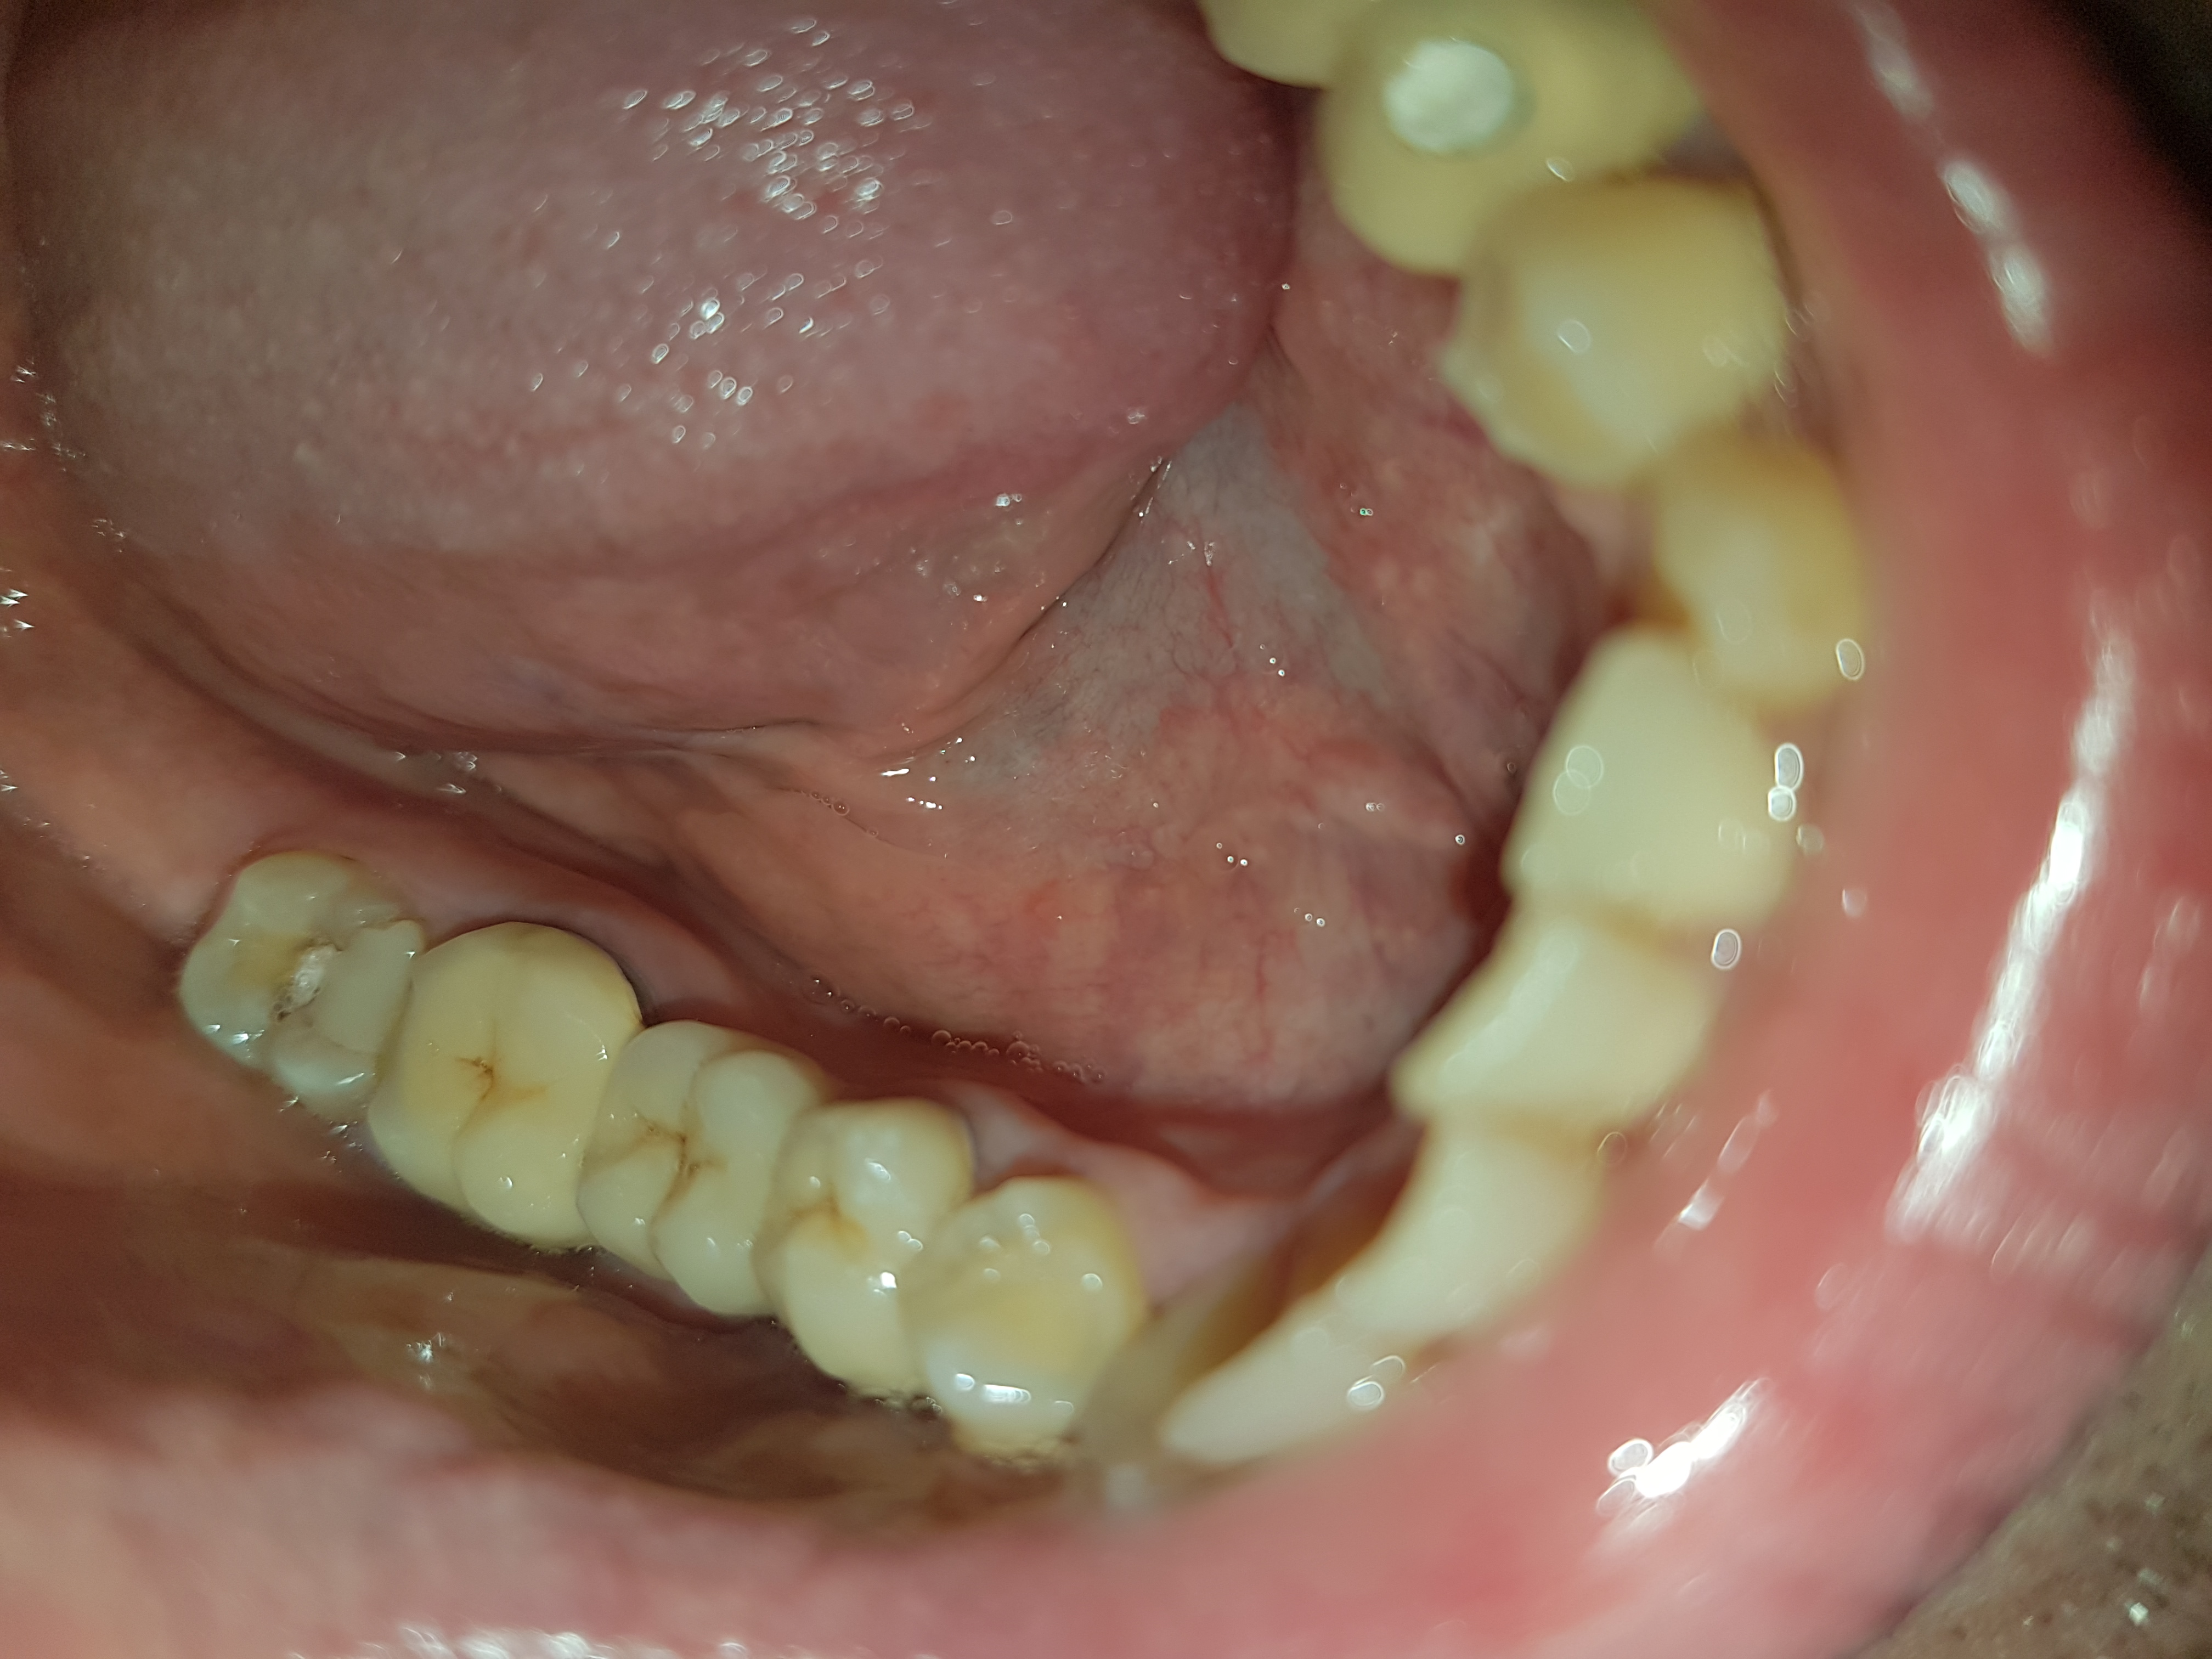

Buongiorno gentili Dottori, recentemente mi sono recato dal dentista per dei dolori che avvertivo sotto ad un ponte definitivo che portavo da oltre sette anni e che non mi aveva mai dato problemi. Egli per vedere cosa c'era ha provato a rimuovere il ponte ma lo ha rotto, curvandosi un pò ed uscendo il metallo fuori come da foto che vi allego qui (in una delle foto ho allegato anche il ponte sano che ho all'altro lato). Dopo mi ha messo del nuovo cemento provvisorio perché si era consumato (secondo lui la causa dei miei dolori) e mi ha rimesso il ponte rotto in attesa di vedere l'evolvere della situazione. Il ponte me lo ha limato per adattarlo alla bocca dato che si era un pò spanato. Da una settimana porto questo ponte un pò rotto e con il metallo fuoriuscito, non sento dolori nel mangiare però vorrei chiedervi se continuare a portarlo per sempre potrebbe essere rischioso. Lui dice che potrebbe anche andare mettendoci di nuovo il cemento definitivo. Per fare un ponte nuovo invece mi ha chiesto una cifra sui 2500 euro. Ora io non so se vale la pena spendere tutti questi soldi per fare un ponte nuovo oppure tenermi questo che già ho. Ma in quest'ultimo caso potrebbero esserci pericoli di carie per i monconi che stanno sotto? Se ad es. il ponte non chiude bene o ha dei forellini invisibili e piccolissimi potrebbero entrare frammenti di cibo con gli anni e i monconi sotto (che sono entrambi già devitalizzati) potrebbero cariarsi e correre il rischio di doverli rimuovere entrambi in futuro? Inoltre, il metallo fuoriuscito potrebbe darmi infezioni o allergie in bocca col passare degli anni? (oppure ingerendone piccoli frammenti col cibo)? Con un ponte un pò rotto potrebbero anche spostarsi gli altri denti in bocca col tempo o arrecare problemi a mandibola e osso? Io non so cosa fare e mi piacerebbe sapere bene dei rischi che potrei correre. Da quando lo porto l'unica cosa che ho notato è come un leggero sapore acido e una specie di liquido che sento in bocca ogni tanto (non so se dipende dal nuovo cemento o dal ponte rotto o altro). Grazie anticipatamente per il vostro aiuto.

Se il vecchio ponte sigilla correttamente sul bordo cervicale dentale e non presenta perforazioni (armatura metallica integra), nessun problema per la sua salute generale ed orale specifica, soltanto un fattore estetico e nulla più (che nella zona dove si trova il ponte si nota relativamente).

Queste valutazioni (sull'integrità ed il sigillo della struttura metallica) deve farla il collega direttamente, dalla foto si capisce relativamente.

Se il sigillo non è adeguato e/o sono presenti perforazioni, allora sicuramente il ponte deve essere rifatto.

Il ponte ha anche un forellino sul premolare che era stato fatto forse in precedenza per la devitalizzazione di questo elemento. Il sapore spiacevole che sente in bocca probabilmente dipende dal fatto che il cemento provvisorio con cui è fissato, non chiude bene. Io farei così: radiografie endorali fatte dal dentista per essere sicuri che le devitalizzazioni abbiano avuto buon esito (cosa non scontata specie se c'era una infezione) - eventualmente attesa di due o tre mesi con il ponte attuale, assicurandosi che sia ben cementato e saldo col cemento provvisorio - poi rifacimento di ponte nuovo. Tutto sommato questo ponte ha fatto una riuscita discreta, sette anni. Poteva durare molto di più se non ci fossero state tutte queste necessità di reintervenire. Visto che lei ha solo 30 anni, mi assicurerei di avere un ponte perfetto...

Da quello che ho capito non si è solo danneggiata la ceramica, ma anche la sottostruttura del ponte ( il ponte che tocca prima e lo sente non in posizione ma spostato...), ciò significa che non ha piu' un intimo rapporto con i monconi sottostanti, e questo può determinare problematiche quali infiltrazioni degli stessi a lungo termine, anche se non è possibile darle una tempistica esatta di ciò. A mio modesto parere farei prima un provvisorio da portare a lungo termine (armato) se vuole aspettare per un discorso economico, e successivamente però fare un nuovo ponte in ceramica definitivo.